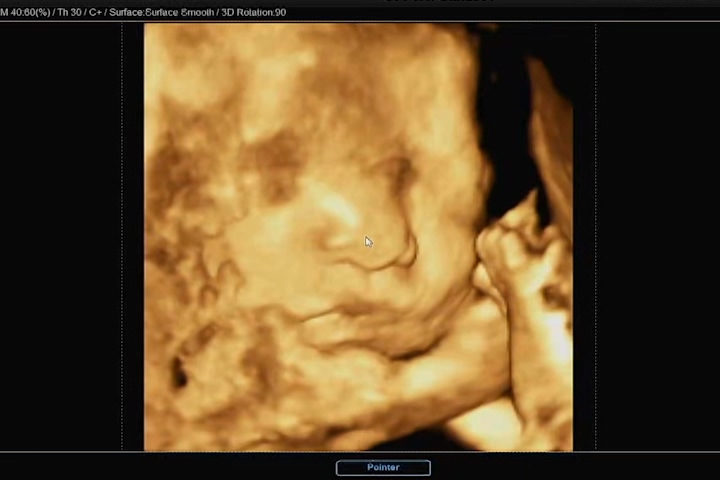

우리 까꿍에 엄마 뱃속의 태반에 머리를 기대고 한쪽 손을 올리고 있어 깔끔하게 얼굴을 보지 못했지만, 나름 만족하게 얼굴을 볼 수 있었다. 사실 이번 초음파 사진 정도까지도 기대하지 않고, 코와 입술 살짝만 나왔으면 좋겠다 했건만 그 이상의 모습도 보여줬다.

잠을 자고 있는지 평소에 비해 움직임이 없던 까꿍이. 보통 3D 초음파는 눈을 감고 있기 때문에 눈 부분은 디테일하게 나오지 않는다고 하셨다. 그래도 영상 중간중간과 초음파 사진에는 눈 윤곽도 나와있어서 얼굴의 형태를 느낄 수 있었다.

입술은 아내를 닮은 것 같고, 코는 나를 닮은 것 같고..ㅎㅎ 서로가 서로를 닮았다며 말했다. 우리 둘을 닮은 아이 아직은 신기하고 귀엽기만 했다. 3D 초음파 검사비용은 병원마다 상이하지만 우리가 다니는 산부인과에서는 6만원이었다.